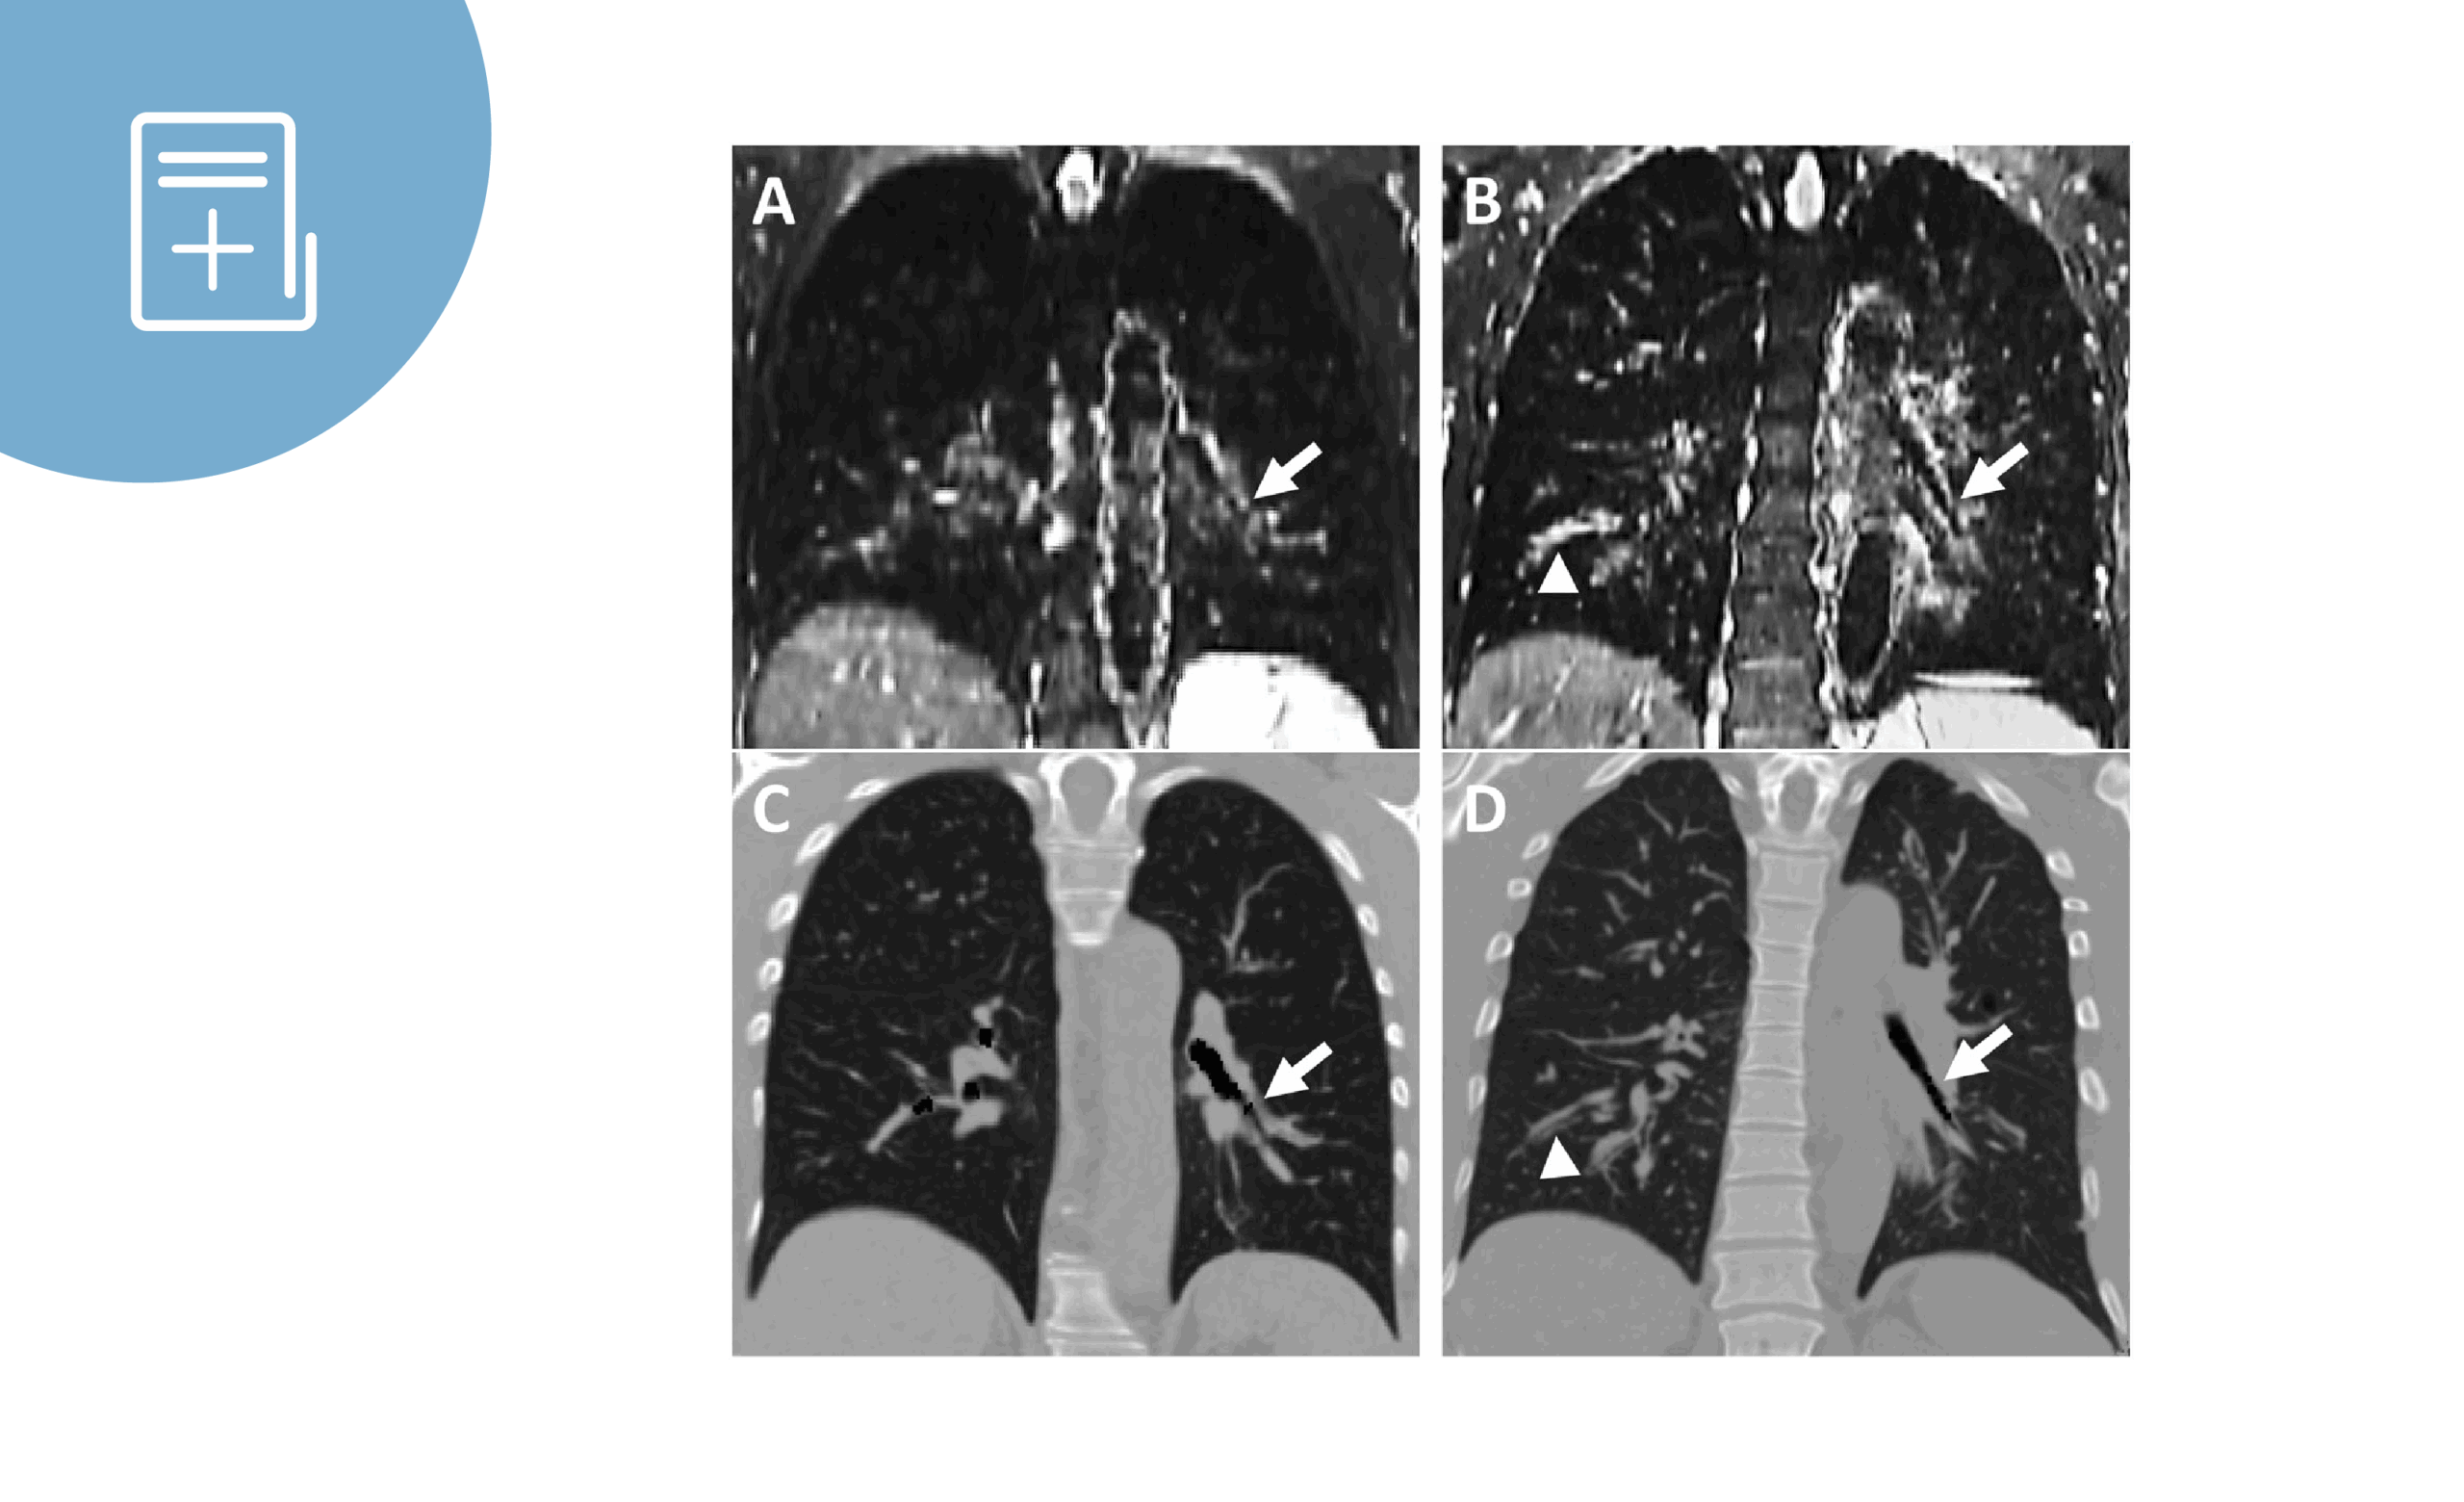

Señal de resonancia magnética T2W de la pared bronquial como nuevo biomarcador de imagen del asma grave

Artículo: Bronchial wall T2w MRI signal as a new imaging [...]

Por |2025-07-08T12:38:55+02:008 de julio de 2025|Resumen de artículo|Comentarios desactivados en Señal de resonancia magnética T2W de la pared bronquial como nuevo biomarcador de imagen del asma grave